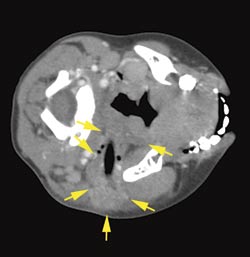

Tilstanden ble nå oppfattet som så alvorlig at det var nødvendig med videre utredning med CT-undersøkelse. CT-bildene viste en stripeformet luftholdig forandring i vevet fra venstre tinningbein til svelget (fig 1). Dette ble oppfattet som et penetrerende fremmedlegeme. Pasienten ble overført med luftambulanse til Øre-nese-hals-avdelingen ved Haukeland Universitetssjukehus. Behandling med antibiotika intravenøst ble startet før transporten.

Ny gjennomgang av CT-undersøkelsen viste en tydelig stikkanal, som angitt, men det var ikke mulig utifra CT-bildene å avgjøre hva slags fremmedlegeme dette kunne være (fig 1). Radiologen antydet at det kunne være et plastrør eller et annet luftholdig og langt fremmedlegeme. Pasientens mor kunne fortelle at det hadde vært noen kvister under treet der han falt og man mistenkte derfor at det var en kvist som vistes som luft på CT-bildet.